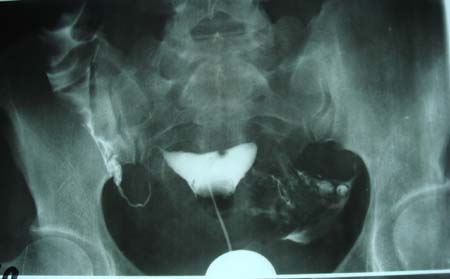

以下是引用dyqct在2009-8-23 16:17:00的发言:[br]考虑:1、造影剂进入腹腔、结肠旁沟、肝周;[br] 2、子宫明显增大(腺肌增生症?);[br] 3、膀胱显影是由于造影剂吸收后经肾分泌进入膀胱的;[br] 4、建议mri检查子宫。